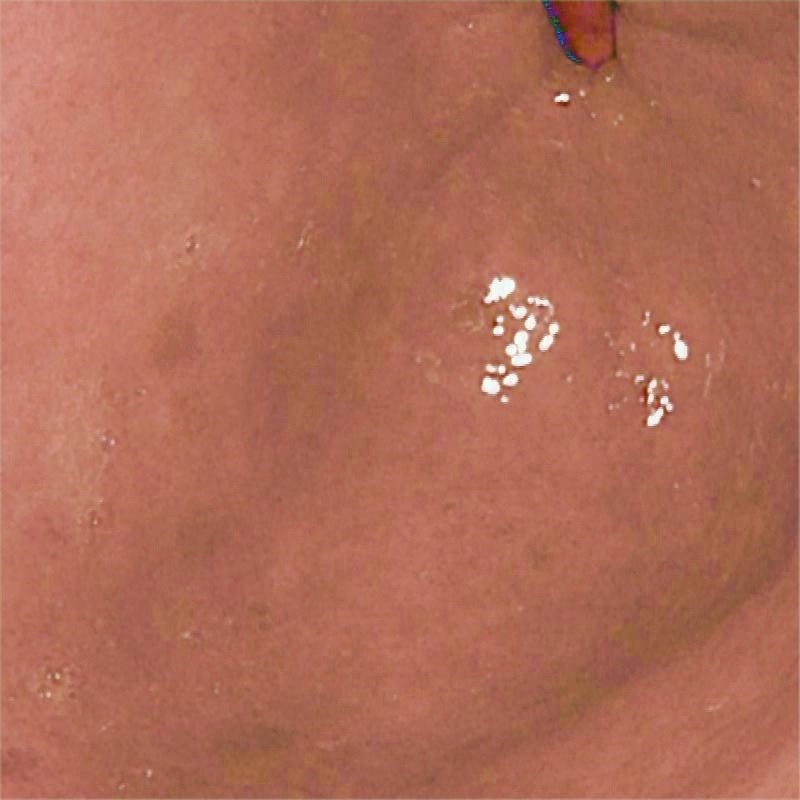

To validate the effectiveness of each module introduced in the proposed network, we conducted an ablation study involving the following two experiments: 1) Without Cross-attention: We removed cross-attention from the model. 2) Without SSM: We removed SSM from the model using a conventional linear layer in its place. Table 2 and Figure 3 compares our method with two ablation studies.

| (a) Input | (b) w/o Cross-attention | (c) w/o SSM | (e) Ours | (f) GT |

| (32.11/0.9498) | (33.31/0.9510) | (35.33/0.9850) | 41.50/0.9899 | (/1) |